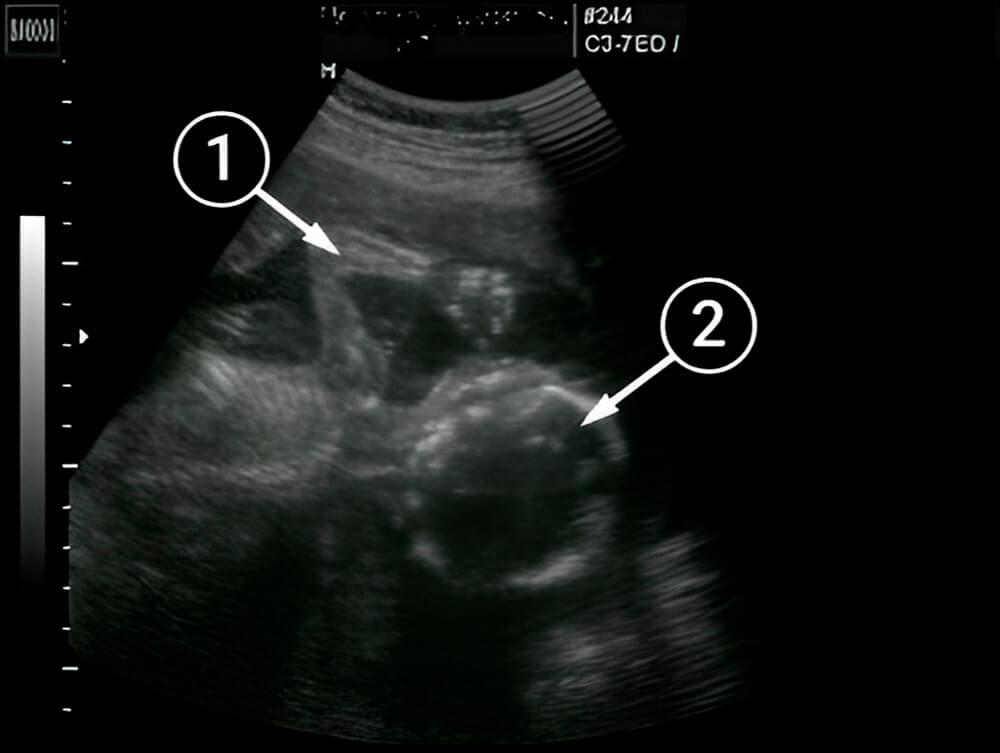

¿Qué se puede ver en la ecografía/ultrasonido?

El bebé se acuesta de espaldas a la pantalla, lo que permite ver el hombro izquierdo, la axila, el antebrazo, el codo y la muñeca. El cuello es más fácil de apreciar, alrededor del cual la grasa subcutánea comienza a depositarse poco a poco.